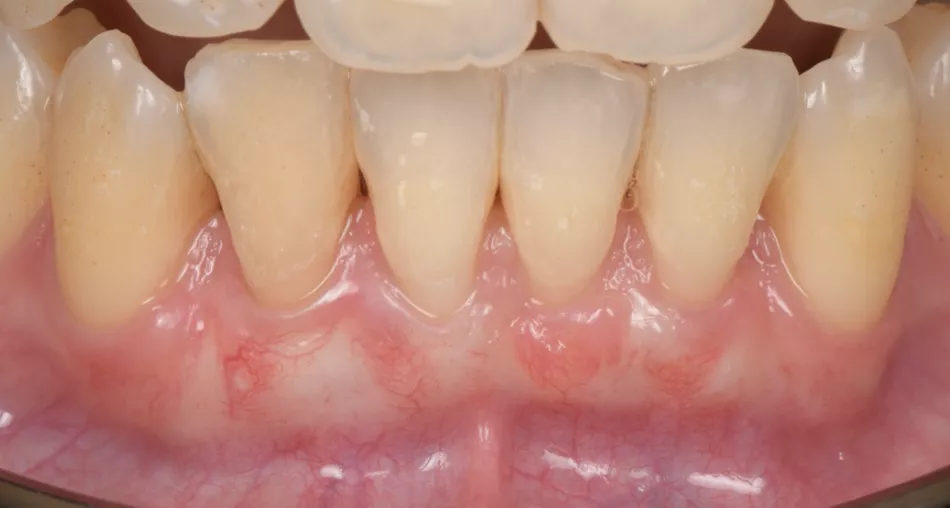

Clinical outcomes were satisfactory. During the one-year postoperative assessment, an improved gingival condition was observed, including a certain degree of root coverage, together with an increased attached and keratinized gingival width, with no evidence of frenum or muscle pull (Fig. 9). The patient expressed how glad she was due to the resolution of the pain when brushing her teeth: “Thanks to the treatment, now I am more confident and happier, because I’ve learnt how to clean my teeth properly, and without any pain!”.

Fig. 9